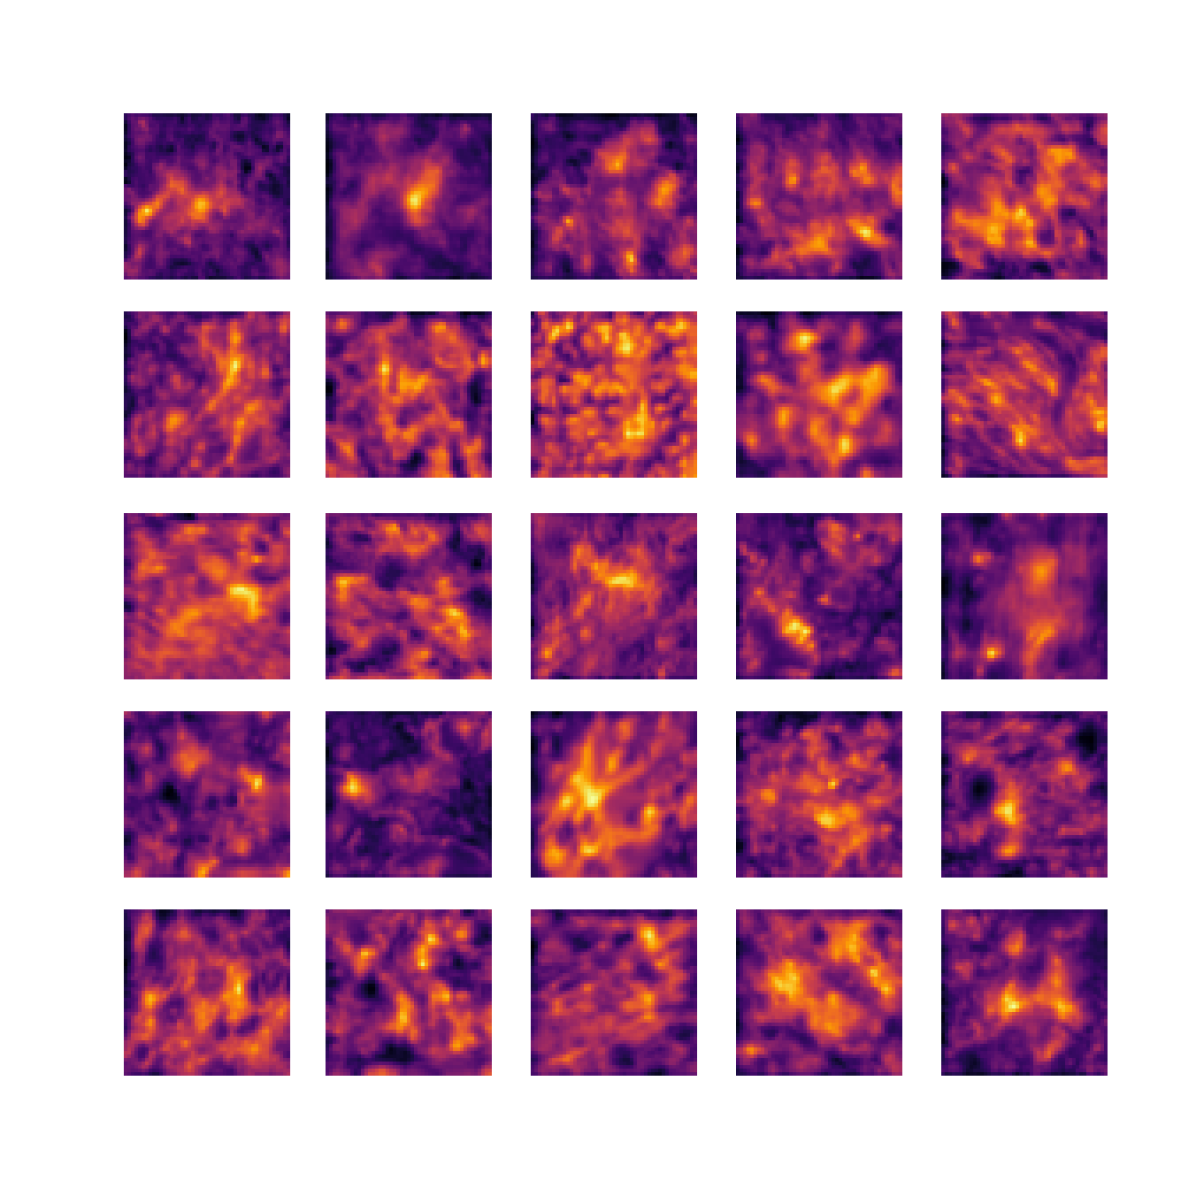

We also analyse the activation maps for each model using GradCAM as described in section S3. This offers more insight into the areas of the image which are contributing most heavily to the models’ representations. In Figure 4(b) we present some representative examples, however, a larger selection which was chosen at random is presented in Figures S10 to S25. The larger selection makes it easier to see the emergent patterns, including that privileged Siamese models tend to mainly identify features which are strongly present in both inputs, while unprivileged Siamese models tend to learn more diffuse features that are not specific to one cell phenotype or image region. TriDeNT ♆ incorporates both sets of features, learning both features specific to the privileged data and more the general features associated with unprivileged Siamese networks.

We can see in Figure 4(b) panel A that for ERG, the privileged Siamese model focuses almost exclusively on any nuclei which could be endothelial cells. As there are very few endothelial cells in the dataset, it could be an effective strategy to identify anything that could potentially be an endothelial cell to minimise the difference between the representations of the H&E model and the IF mask model. In the corresponding unprivileged Siamese image, we see that the model identifies some of these nuclei, albeit less strongly, but also focuses heavily on the other tissue and even the background, while strongly fixating on two spots of debris in the center of the image. This model has less ‘incentive’ to learn the weak features related to endothelial cells as these occur rarely and are not easy to detect, while more generic strong features such as the presence of connective tissue and the prevalence of background are more common and predictable from augmented images. We see that TriDeNT ♆ combines these two feature sets, strongly identifying nuclei while also identifying the connective tissue.

In panel C we see a similar pattern, with the privileged Siamese model fixating solely on the nuclei, while the TriDeNT ♆ model takes a more balanced approach. The unprivileged Siamese model appears to focus on a single cluster of nuclei while neglecting others, and similarly identifies an area of fibroblasts with its distinctive pattern but does not others.

In contrast to panels A and C which represent models with poor privileged Siamese results, panels B and D represent models whose privileged Siamese results were comparable to both TriDeNT ♆ and even the supervised baseline. It is therefore interesting to note that there are far more similarities between the privileged Siamese and TriDeNT ♆ models in both cases. Particularly in panel B, TriDeNT ♆ and the privileged Siamese model return virtually identical heatmaps, with both strongly identifying epithelial nuclei and neglecting the same areas of connective tissue. The unprivileged model in this case appears to focus solely on the centre of the image, giving a significantly different heatmap to the other panels.

Panel D again shows the previous pattern, with the privileged Siamese model identifying the features strongly present in the privileged data – fibroblasts – while neglecting the nuclei present. TriDeNT ♆ also strongly identifies the connective tissue, but, unlike the privileged Siamese model, does not completely neglect the nuclei. The unprivileged Siamese model primarily identifies background, and does not appear to identify the nuclei in this example.